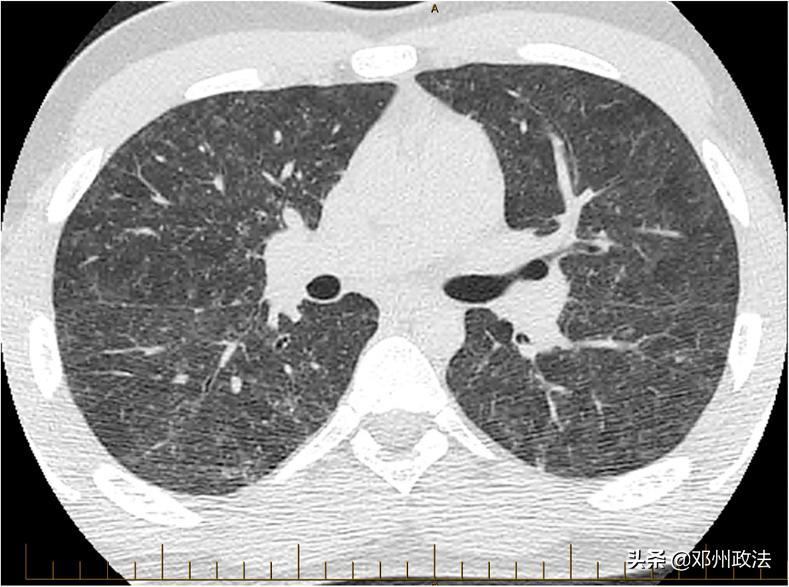

胸部计算机断层扫描(CT)扫描显示,双侧对称的弥漫性磨玻璃样病变,但没有看到明显的小结节。既不像是常见的肺炎表现,也没有结核病的证据。

患者的胸部 CT(图源:参考文献)